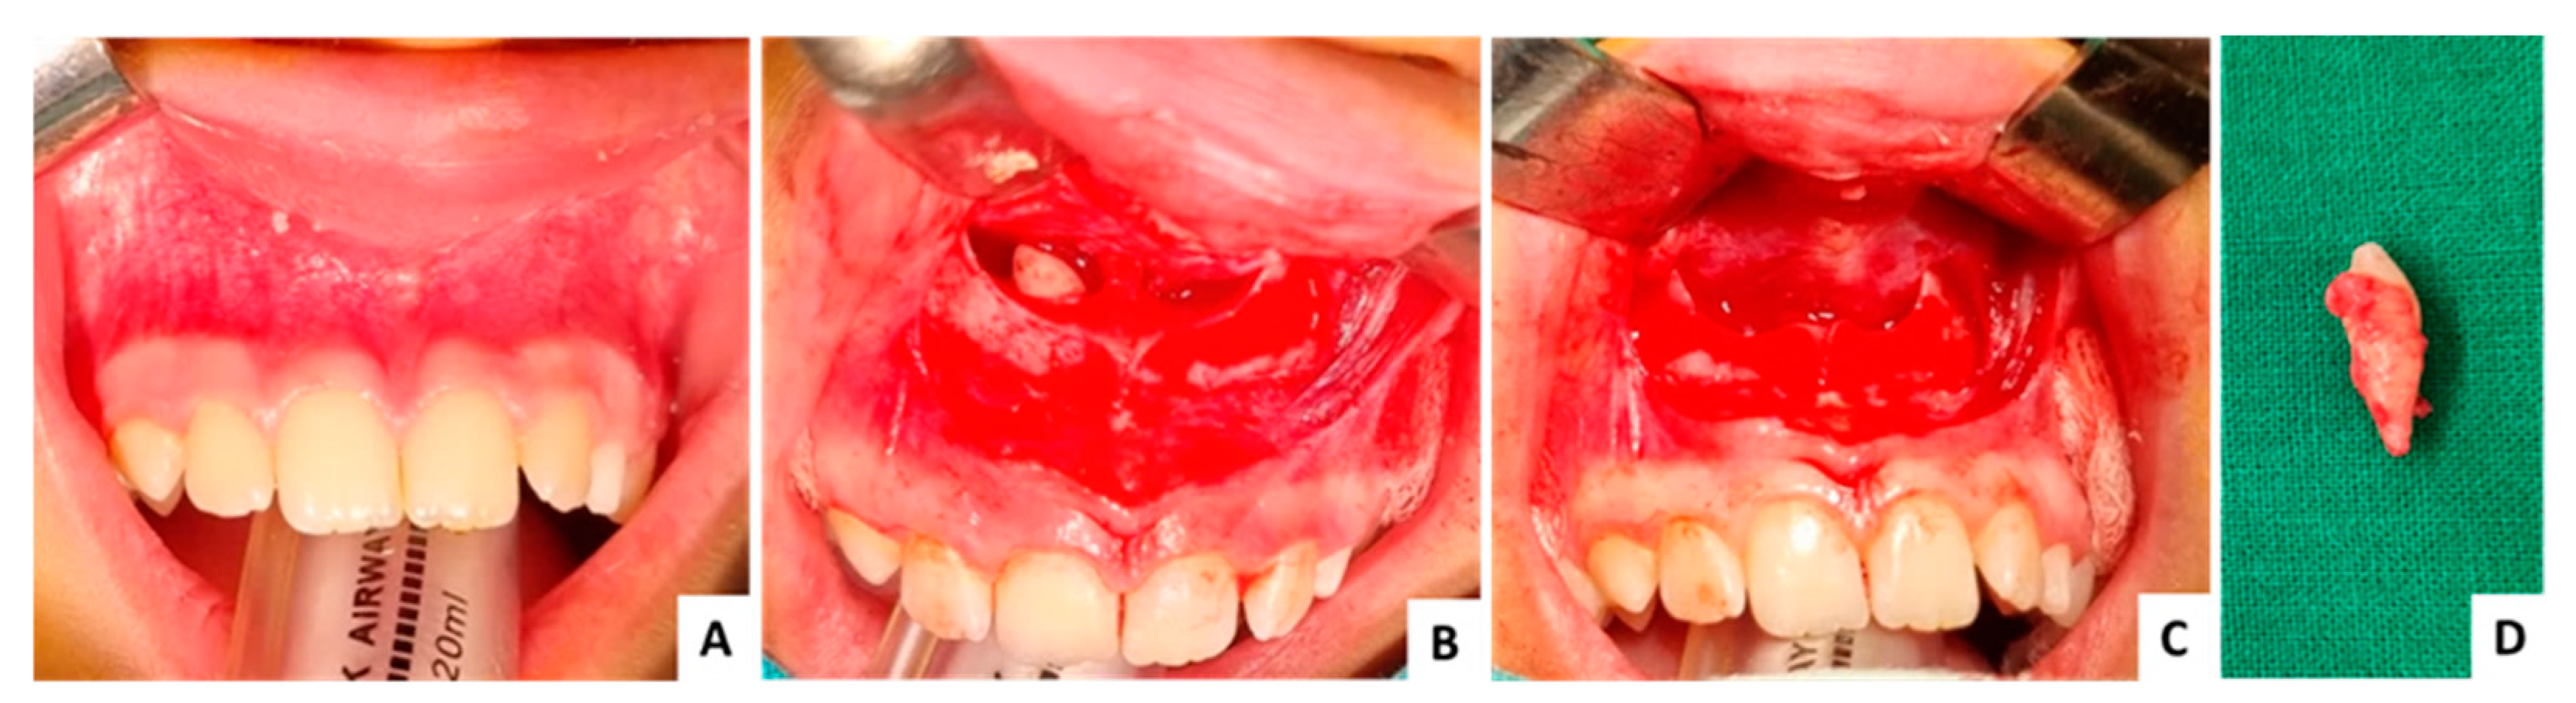

3.3. Case 3 (Figure 9, Figure 10 and Figure 11)